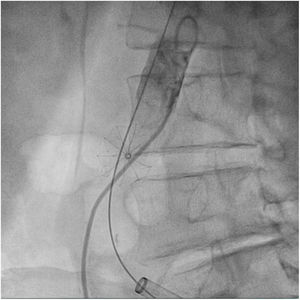

El paciente se traslada a la sala de hemodinamia donde se intenta la extracción del dispositivo. Se utilizan diferentes catéteres lazo de 10, 25 y 30 mm, así como lazos de fabricación con guías largas y cortas intentando movilizar el dispositivo desde diferentes accesos vasculares (acceso bifemoral 6 y 18 Fr y radial 6 Fr) (figuras de la 1 a la 4). Se produce como complicación disección de aorta abdominal con extensión a arteria ilíaca común derecha (figuras 5 y 6) y pérdida total del flujo en extremidad inferior ipsilateral con signos y síntomas de isquemia arterial aguda, por lo que el paciente es trasladado de forma urgente al quirófano de angiología y cirugía vascular. Se realiza disección de aorta abdominal infrarrenal vía laparotomía media con aortotomía longitudinal en el lugar de la localización del cuerpo extraño visualizándose el dispositivo migrado anclado a la íntima-media de la pared arterial. Se procede a su extracción y posteriormente se realiza cierre de aortotomía con parche de pericardio bovino fijando la disección y corrigiendo así el defecto (figuras de la 7 a la 9). El paciente sale de quirófano con pulso pedio bilateral y excelente perfusión distal.